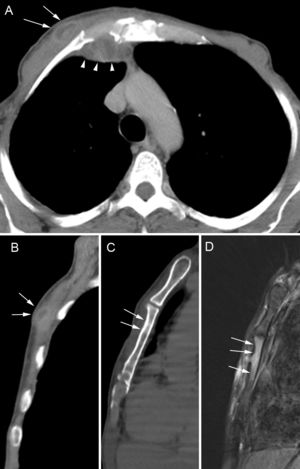

En el TAC torácico se observó acumulación de líquido en los tejidos blandos de la pared torácica anterior derecha, junto a la articulación condroesternal homolateral y engrosamiento cortical del cuerpo esternal (fig. 1A-C). Los pulmones tenían aspecto normal. En una RM sagital en T2 con saturación grasa se observó edema en la médula ósea del esternón (fig. 1D) y una biopsia de la lesión esternal mostró inflamación crónica granulomatosa y purulenta con necrosis caseosa. Tanto la secreción esternal como la biopsia fueron positivas para Mycobacterium tuberculosis y las bacterias eran sensibles a los fármacos antituberculosos. El paciente recibió tratamiento antituberculoso con 4 fármacos (isoniazida, pirazinamida, etambutol y rifampicina) durante 2 meses (fase intensiva) e isoniazida y rifampicina durante 4 meses (fase de mantenimiento), tras lo cual se alcanzó remisión clínica completa. Un año después el paciente permanecía asintomático.

Imágenes del TAC torácico axial (A) y sagital (B) reformateadas que muestran una acumulación hipodensa en los tejidos blandos de la pared torácica anterior derecha, al lado del esternón (flechas). La acumulación se comunica con otra parietal interna (puntas de flecha). Otra imagen sagital (C) muestra el engrosamiento de hueso cortical en la superficie anterior del cuerpo esternal (flechas). Una imagen de RM sagital en T2 con saturación de grasa (D) muestra señal de alta intensidad de la médula ósea del esternón.